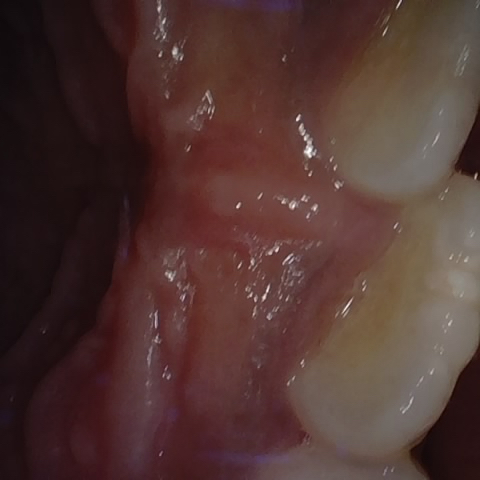

Annotated as "Good"